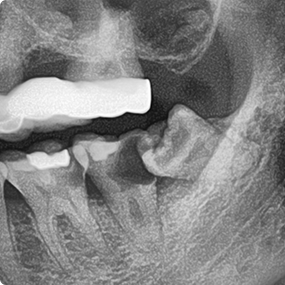

為了健保患者拔智齒的安全,遠離唇麻、舌麻、口鼻竇炎、大出血...等併發症,

☆本院特別巨資增設 ”千萬級3D AI透視電腦斷層”,並配合“成骨膠原蛋白”施作 (上述兩項目前健保無給付),讓您遠離神經傷害、口鼻竇(炎)相通...等併發症,除健保之外,難免會有避免併發症風險的自費項目,網路上經常會有看到智齒拔完後唇麻、舌麻、口鼻竇相通等併發症,在本院嚴格自我要求下,此類併發症在本院幾乎趨近於零。

外面拔完時常術後唇麻舌麻,本院發生趨近於零